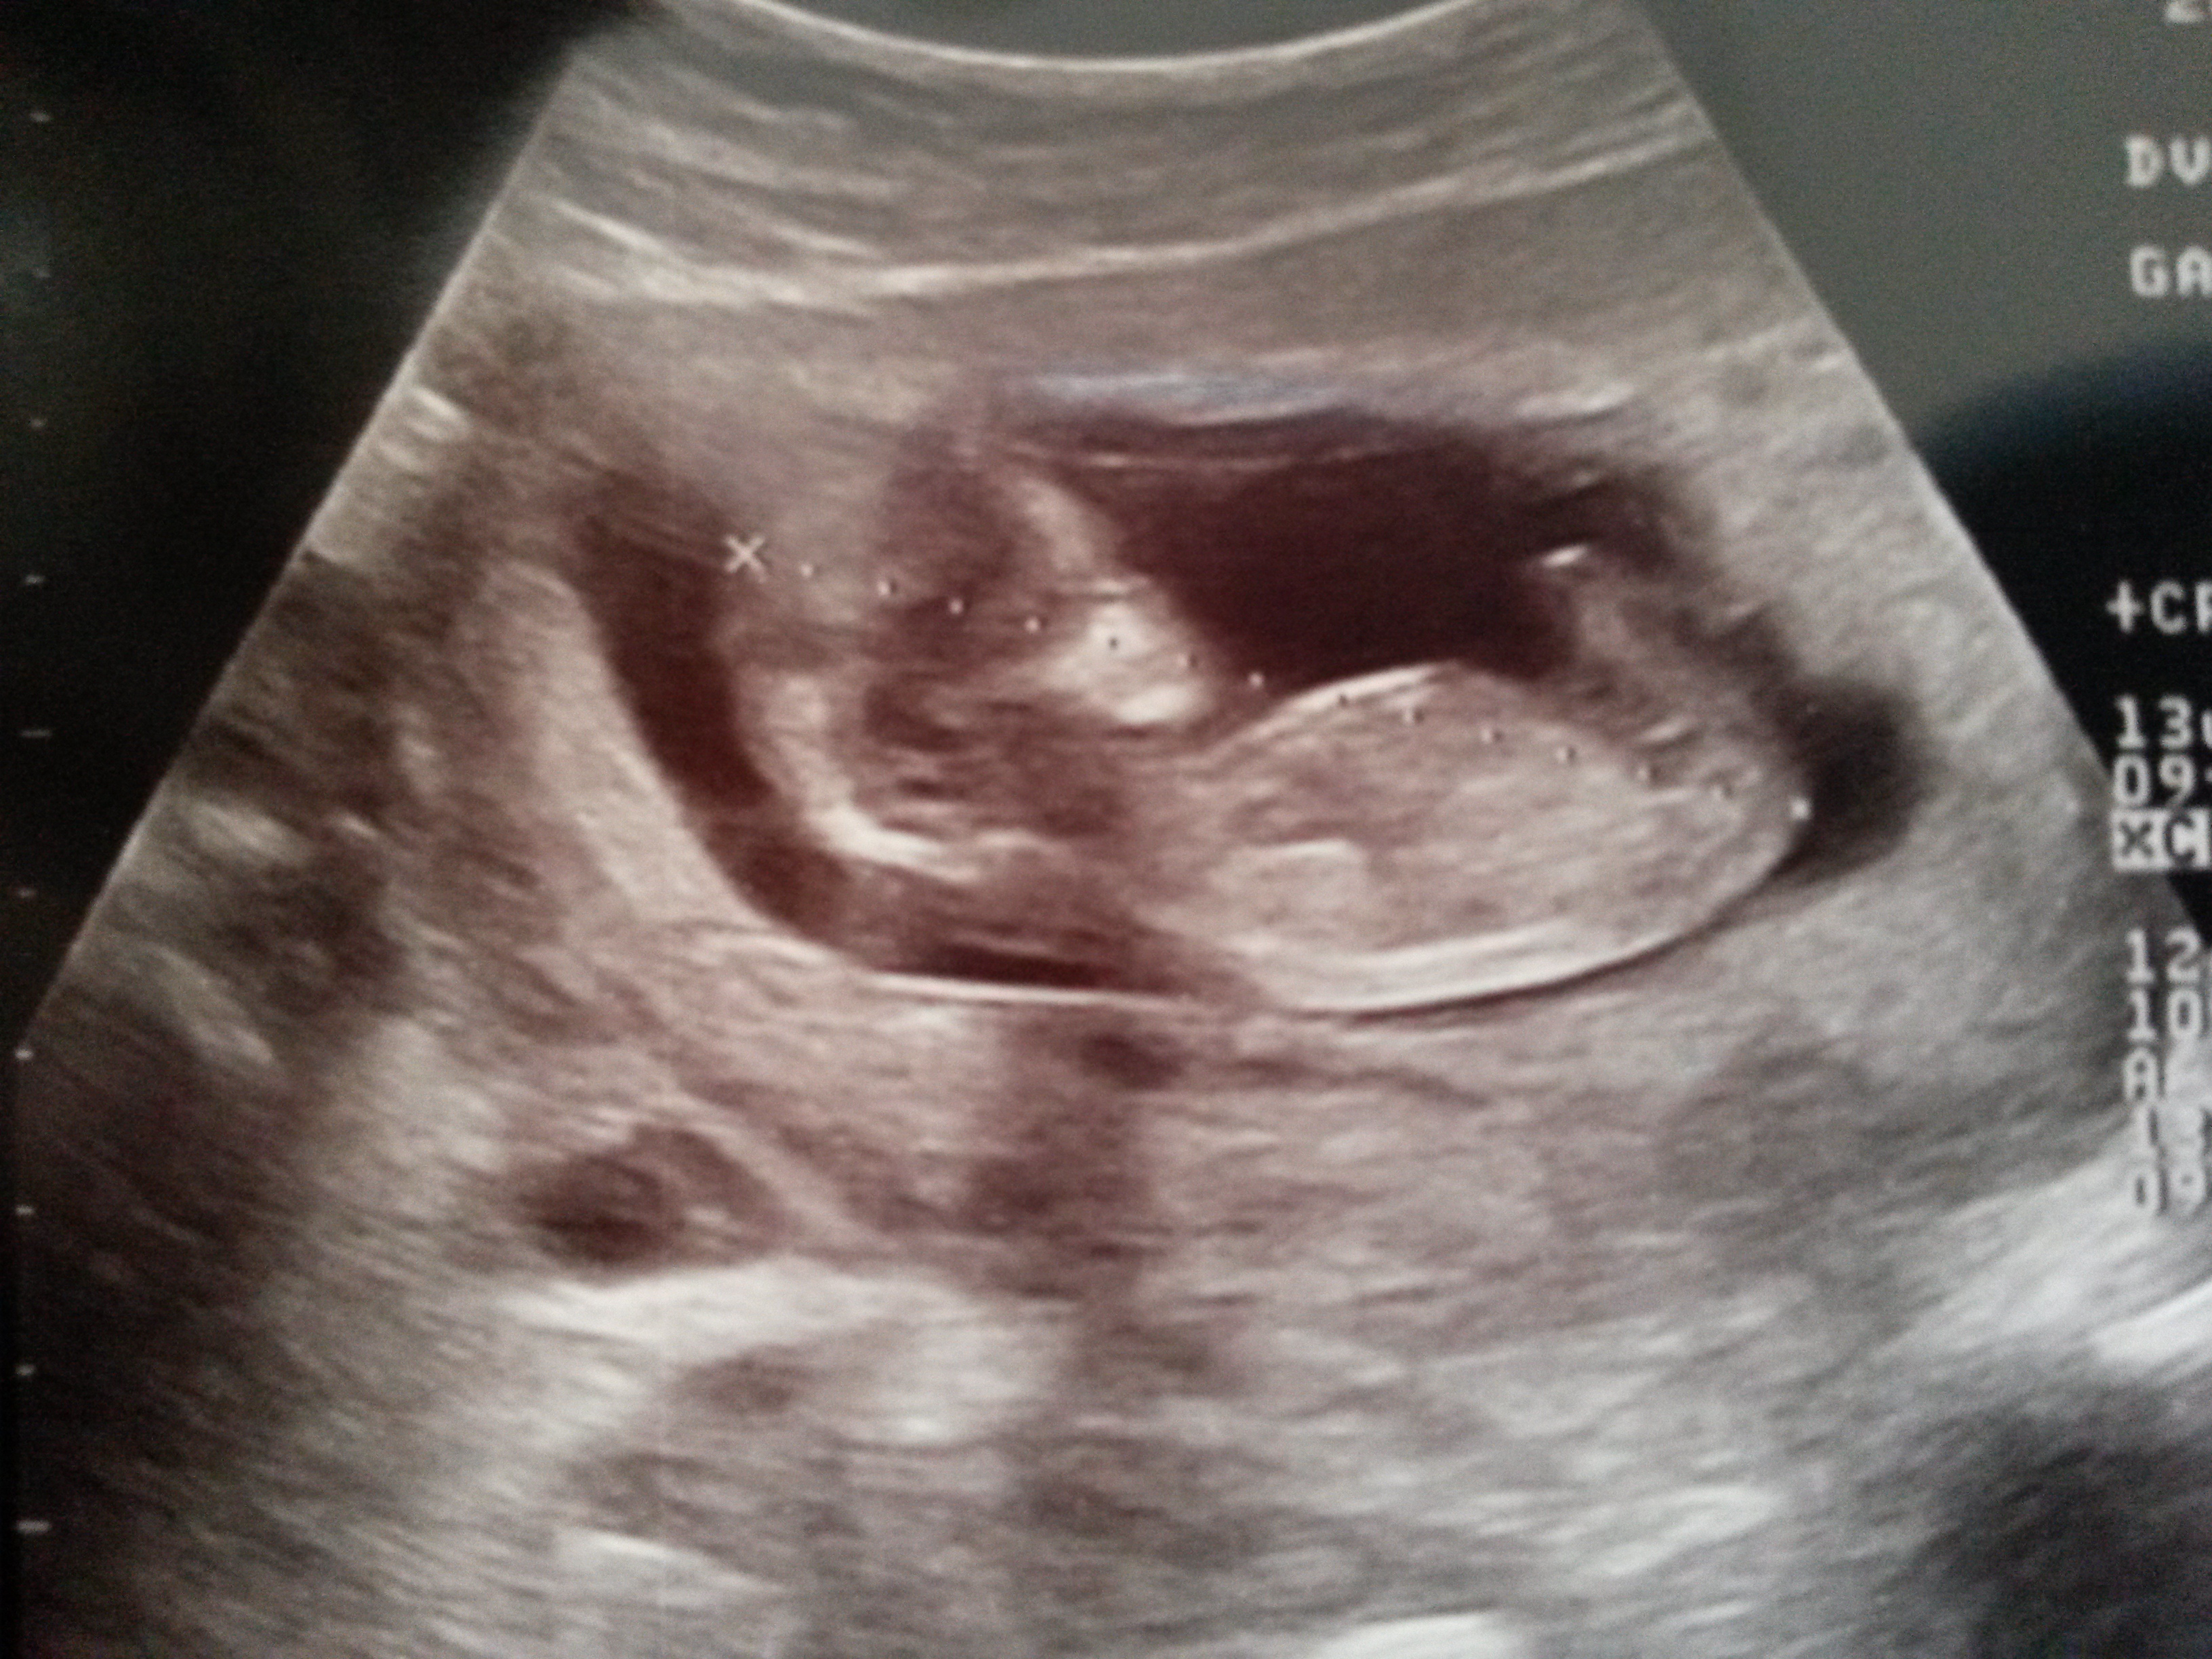

Personally I do not see a nub on this photo. Maybe someone else does?

And if you see one, maybe you can als tell me what you think it is? A girl or a boy?

There is a small partial there. Looks girly so hopefully!